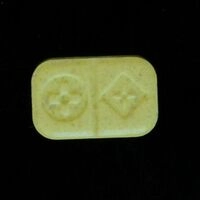

Baza tabletek Ecstasy zawiera analizy laboratoriów i użytkowników. Wyniki to ostrzeżenia. Żadna substancja nie jest w 100% bezpieczna. Badaj substancje przed zażyciem. Sprawdź narkotest.

Zastrzeżenie: Informacje przedstawione na tej stronie nie mają na celu promocji zażywania narkotyków. Wiele wymienionych substancji jest nielegalne według prawa krajowego i międzynarodowego, posiadanie tych substancji jest karane przez prawo. Nigdy nie zakładaj, że substancja jest bezpieczna. Tabletki Ecstasy (extasy, XTC, emka, molly) powinny zawierać MDMA ale stężenie, czystość i domieszki bardzo się różnią, nawet jeśli próbki pochodzą z tego samego źródła lub wyglądają podobnie. Chemical Safety sp. z o.o. stanowczo odradza używania jakichkolwiek substancji psychoaktywnych – legalnych lub nielegalnych. Zażywanie substancji psychoaktywnych zawsze jest możliwym do uniknięcia ryzykiem dla zdrowia.